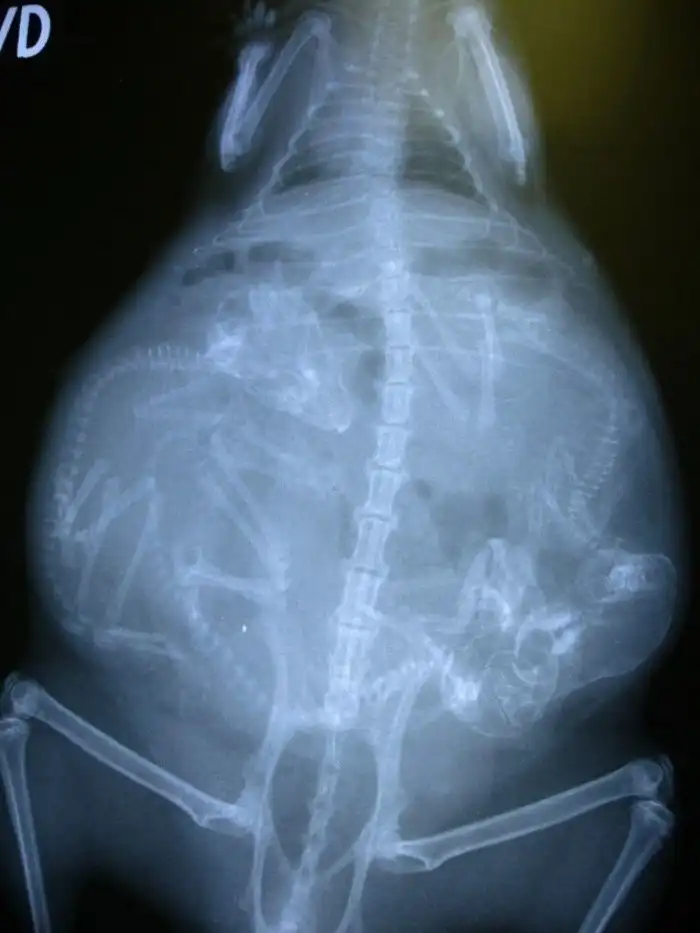

9. Беременная морская свинка